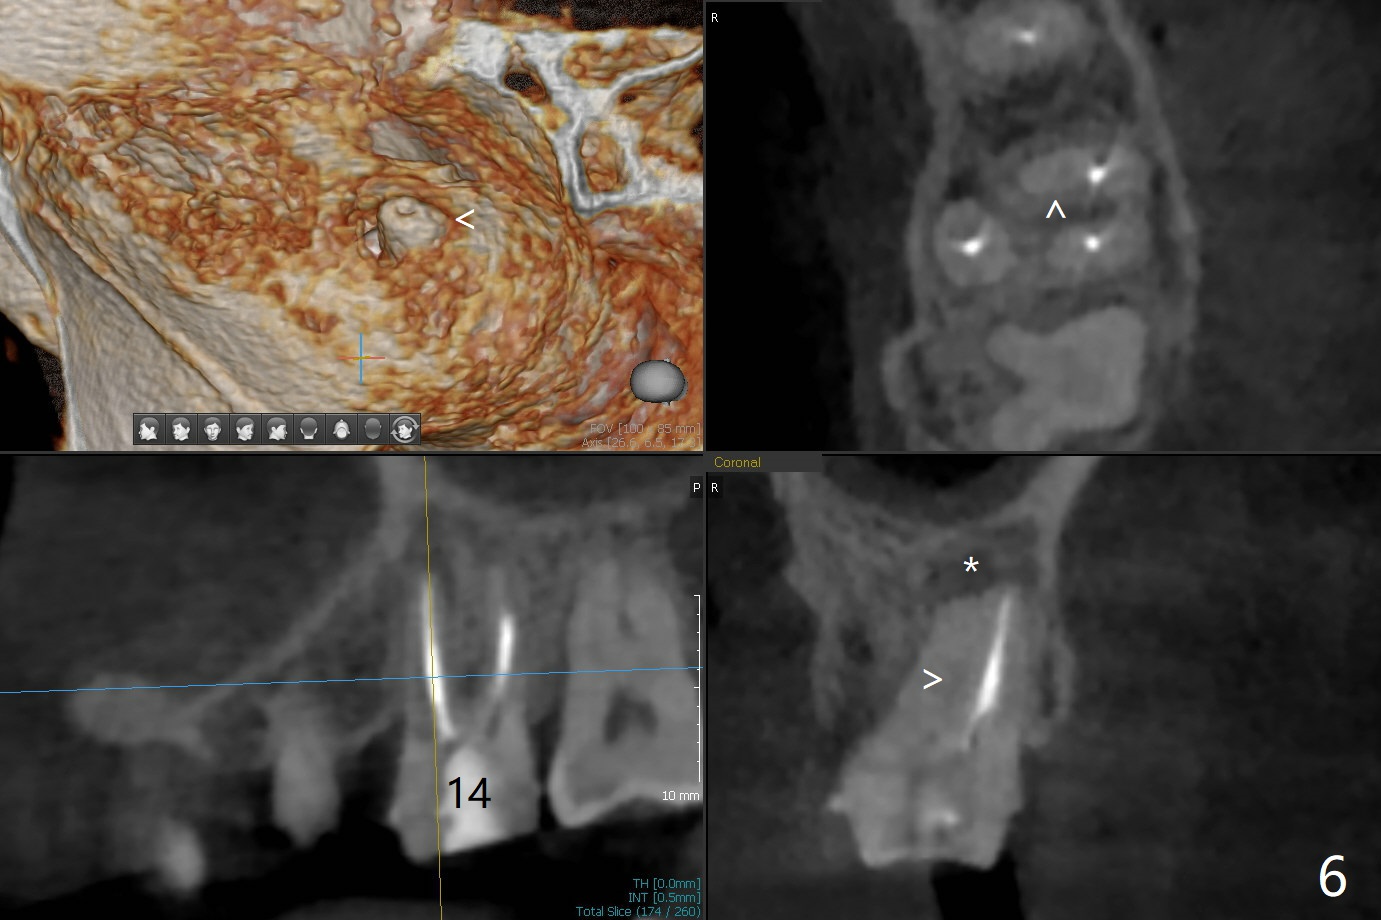

A 44-year-old woman used to have splinted crowns at #13 and 14 (Fig.1). Their dislodgement is due to residual roots at #13 and distal caries at #14 (Fig.2 ^). To avoid the distally curved apex of #12 and to have ideal trajectory of an IBS implant (Fig.4), osteotomy will be initiated in the distopalatal slope of the socket (Fig.3 arrowheads). The patient wants to correct the tooth #8 with rotation (Fig.5), which is due to a mesiodens (Fig.1,2 M). It will be accessed palatal (Fig.5 P). In fact there is percussion at #14 associated with MB2 (Fig.6 arrowheads) and PARL (*).